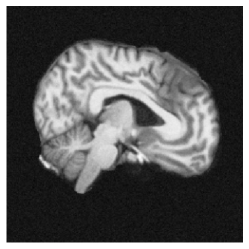

4.1 Datasets

Real-world data. We benchmarked on the OASIS-1 dataset [7], which consists of brain MRI scans of individual patients in different stages of dementia and a healthy control group. We used 5 pairs for hyperparameter tuning and the rest for evaluation. The image dimensions are voxels. Besides the intensity values, each dataset contains segmentations on regions, conducted by experts. We used the skull-stripped, affinely pre-aligned volumes provided in the dataset.

To generate the image pairs, the deformation was applied to a zero-padded reference image from the OASIS dataset, to which Gaussian noise with mean zero and standard derivation was added, resulting in a synthetic template image. Some exemplary deformations can be seen in Fig. 10.

|

coronal |

![]() |

|---|---|---|---|

axial |

central |

| reference | generated deformation | overlay |